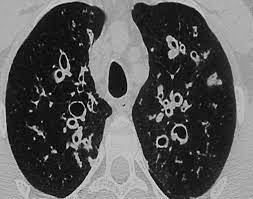

La distribución de la bronquiectasia puede ser variable, pudiendo afectar un solo lóbulo o segmento pulmonar (bronquiectasia localizada) o múltiples lóbulos de un pulmón o incluso ambos pulmones (bronquiectasia difusa). La forma difusa suele estar asociada con enfermedades sistémicas como la fibrosis quística, discinesia ciliar primaria o inmunodeficiencias.

La bronquiectasia asociada con la FQ tiende a ser difusa y afecta múltiples lóbulos pulmonares, debido a la naturaleza generalizada del proceso inflamatorio y destructivo en los pulmones. Además, los pacientes con FQ suelen experimentar episodios recurrentes de exacerbaciones pulmonares y neumonías, que agravan aún más el daño bronquial y promueven la formación de bronquiectasias.